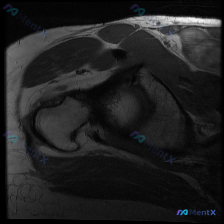

整理了一份肩部MRI病例资料,先放T1冠状位序列的影像描述,大家先不看后续结论,第一眼会优先考虑什么方向? 已知影像基础信息 影像类型:肩关节MRI,T1序列,冠状位 可见结构:肱骨头、关节盂、肩峰、锁骨远端对位基本正常 核心观察点提示 1. 冈上肌腱肱骨大结节附着处存在形态及信号异常 2. 肩袖肌...